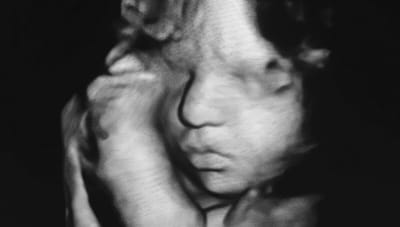

Gravidanza: dalla 17ª alla 20ª settimana